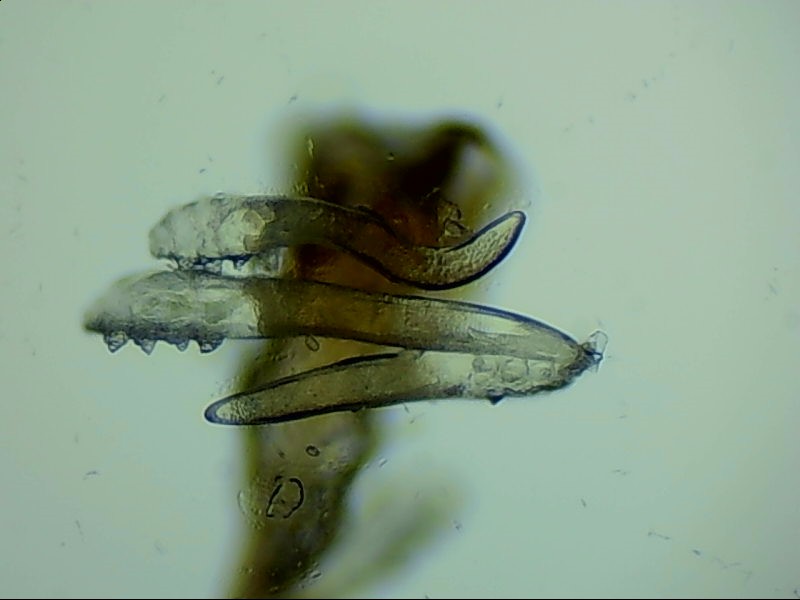

蠕形螨是螨蟲的一種,主要寄居在毛囊中。蠕形螨以分泌的油脂、分泌物為食,所以眼部寄居著蠕形螨的患者多有亂睫或睫毛脫落的癥狀。

蠕形螨寄居后,它們以睫毛毛囊里面的油脂為食。隨著油脂的缺失,睫毛會(huì)長的東倒西歪,如果毛囊里的油脂都被吃光了,就會(huì)出現(xiàn)睫毛脫落這種蠕形螨性瞼緣炎的典型癥狀。

身體健康時(shí),蠕形螨就吃吃油脂,夜里爬出來活動(dòng)、交配,與我們相安無事,一旦身體的免疫力下降,蠕形螨的活動(dòng)、產(chǎn)的卵、排泄的廢物和分泌的分泌物都會(huì)引起過敏反應(yīng)?;颊邥?huì)出現(xiàn)眼癢、異物感、眼干、瞼緣充血、鱗屑、睫毛根部袖套狀分泌物及睫毛脫落等癥狀,嚴(yán)重者可并發(fā)結(jié)膜及角膜病變,給生活帶來不便和困擾。